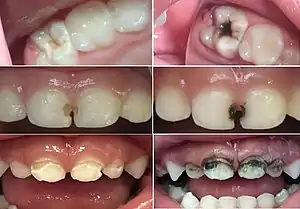

![]() Before (left) and after (right) use of SDF in people with tooth decay | |

| Side effects | Staining of cavities black, metallic taste[1] |

The main side effect of SDF is non-medical and is the prominent black staining of carious tooth tissue where the solution is applied.[24]

SDF will stain most things it touches, including skin, mucous membranes, clothing and work surfaces. Chu et al. reported on the first modern clinical trial of SDF that the stain was generally acceptable and "the presence of darkened teeth was mentioned by around 7% of the parents."[25]